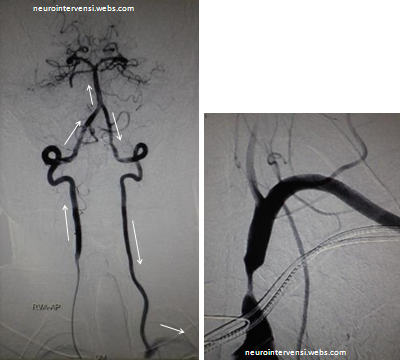

Gambar 1 dan 2

Sirkulasi anterior dari kedua arteri carotis normal,

namun saat dilakukan injeksi kontras dari arteri vertebralis sebelah kanan,

disamping memberikan vaskularisasi pada arteri basilaris serta sirkulasi

distalnya, darah juga mengalir menuju ke arteri vertebralis kontra lateral dan

subclavia kiri (lihat gambar 1 dengan arah panah). Saat dilakukan injeksi

kontras pada subclavia kiri, tampak adanya stenosis yang cukup signifikan pada

subclavia, tepatnya proksimal dari ostium arteri vertebralis kiri (gambar 2).

Kasus ini merupakan gambaran klasik subclavian steal syndrome(SSS).